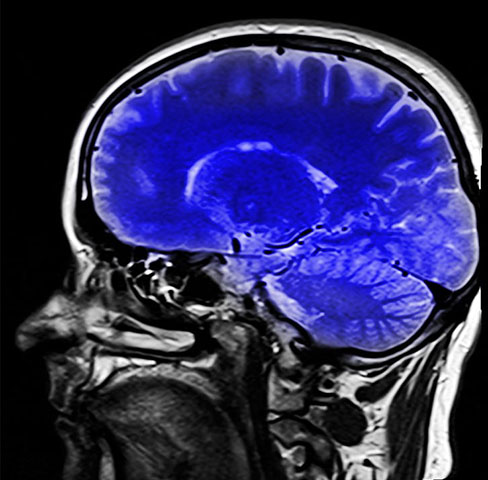

Maurício Kubrusly sofre queda e é levado à UTI na Bahia